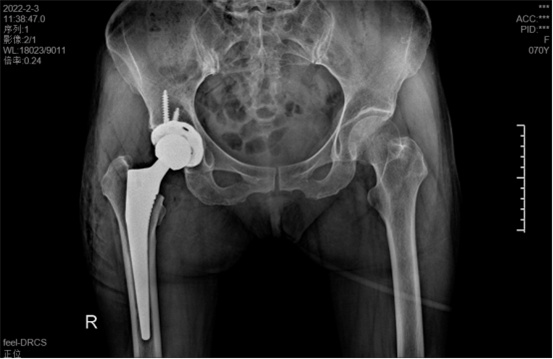

據(jù)羅軍主任介紹,他們首先將鄭阿姨的術前CT數(shù)據(jù)導入到系統(tǒng)中,通過自動識別骨盆和股骨建立了計算機數(shù)字三維模型。AI HIP顯示患者適合使用合適的髖臼杯、股骨柄、標準陶瓷球頭、陶瓷內(nèi)襯,并精準定位了截骨線,有效幫助醫(yī)生在手術中做到精確截骨。

在完善相關檢查充分評估患者身體情況及手術風險后,羅軍主任改變傳統(tǒng)手術方式,在易觀俊主治醫(yī)師、柴重喜醫(yī)師等助手的配合下,為鄭阿姨實施了人工智能規(guī)劃輔助DAA入路全髖關節(jié)置換術。

術中假體植入和術前規(guī)劃完全一致

術中,醫(yī)生在患者髂前上棘外側(cè)切開約8cm長的切口,小心翼翼地利用闊筋膜張肌與縫匠肌之間的間隙露出髖關節(jié)。經(jīng)過一番精細、高難度的操作,成功植入人工髖關節(jié)組件,以取代受損的股骨頭和髖臼。由于手術切口小,肌肉組織未受損,鄭阿姨恢復很快,術后第1天就能下床活動。